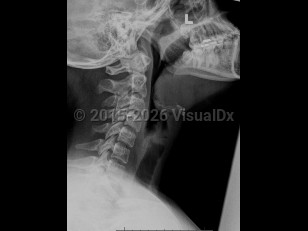

Epiglottitis

Epiglottitis is a potentially life-threatening inflammation of the epiglottis and supraglottic space caused by infection (eg, Haemophilus influenzae type b [Hib]) or injury (eg, foreign body, caustic substance, thermal damage). As the epiglottis swells, it can cause airway obstruction and create a medical emergency. Presenting symptoms include high fever, sore throat, difficulty swallowing, dyspnea, hoarseness, stridor, tachycardia, drooling, and hot potato voice or dysphonia.

Protection of the airway is a priority, and treatment may require placement of an artificial airway, intravenous steroids, antimicrobial therapy to control infection, and surveillance in an intensive care unit. Tracheostomy may be required in severe cases if airway management is not achievable with medical intervention or oral / nasal intubation.